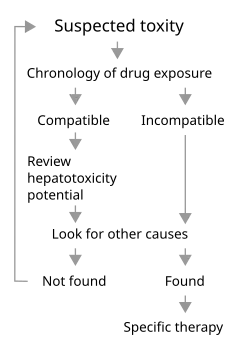

Diagnosis

This remains a challenge in clinical practice due to a lack of reliable markers.[48] Many other conditions lead to similar clinical as well as pathological pictures. To diagnose hepatotoxicity, a causal relationship between the use of the toxin or drug and subsequent liver damage has to be established, but might be difficult, especially when idiosyncratic reaction is suspected.[49] Simultaneous use of multiple drugs may add to the complexity. As in acetaminophen toxicity, well established, dose-dependent, pharmacological hepatotoxicity is easier to spot. Several clinical scales such as CIOMS/RUCAM scale and Maria and Victorino criteria have been proposed to establish causal relationship between offending drug and liver damage. CIOMS/RUCAM scale involves a scoring system that categorizes the suspicion into "definite or highly probable" (score > 8), "probable" (score 6–8), "possible" (score 3–5), "unlikely" (score 1–2) and "excluded" (score ≤ 0). In clinical practice, physicians put more emphasis on the presence or absence of similarity between the biochemical profile of the patient and known biochemical profile of the suspected toxicity (e.g., cholestatic damage in amoxycillin-clauvonic acid ).[48]